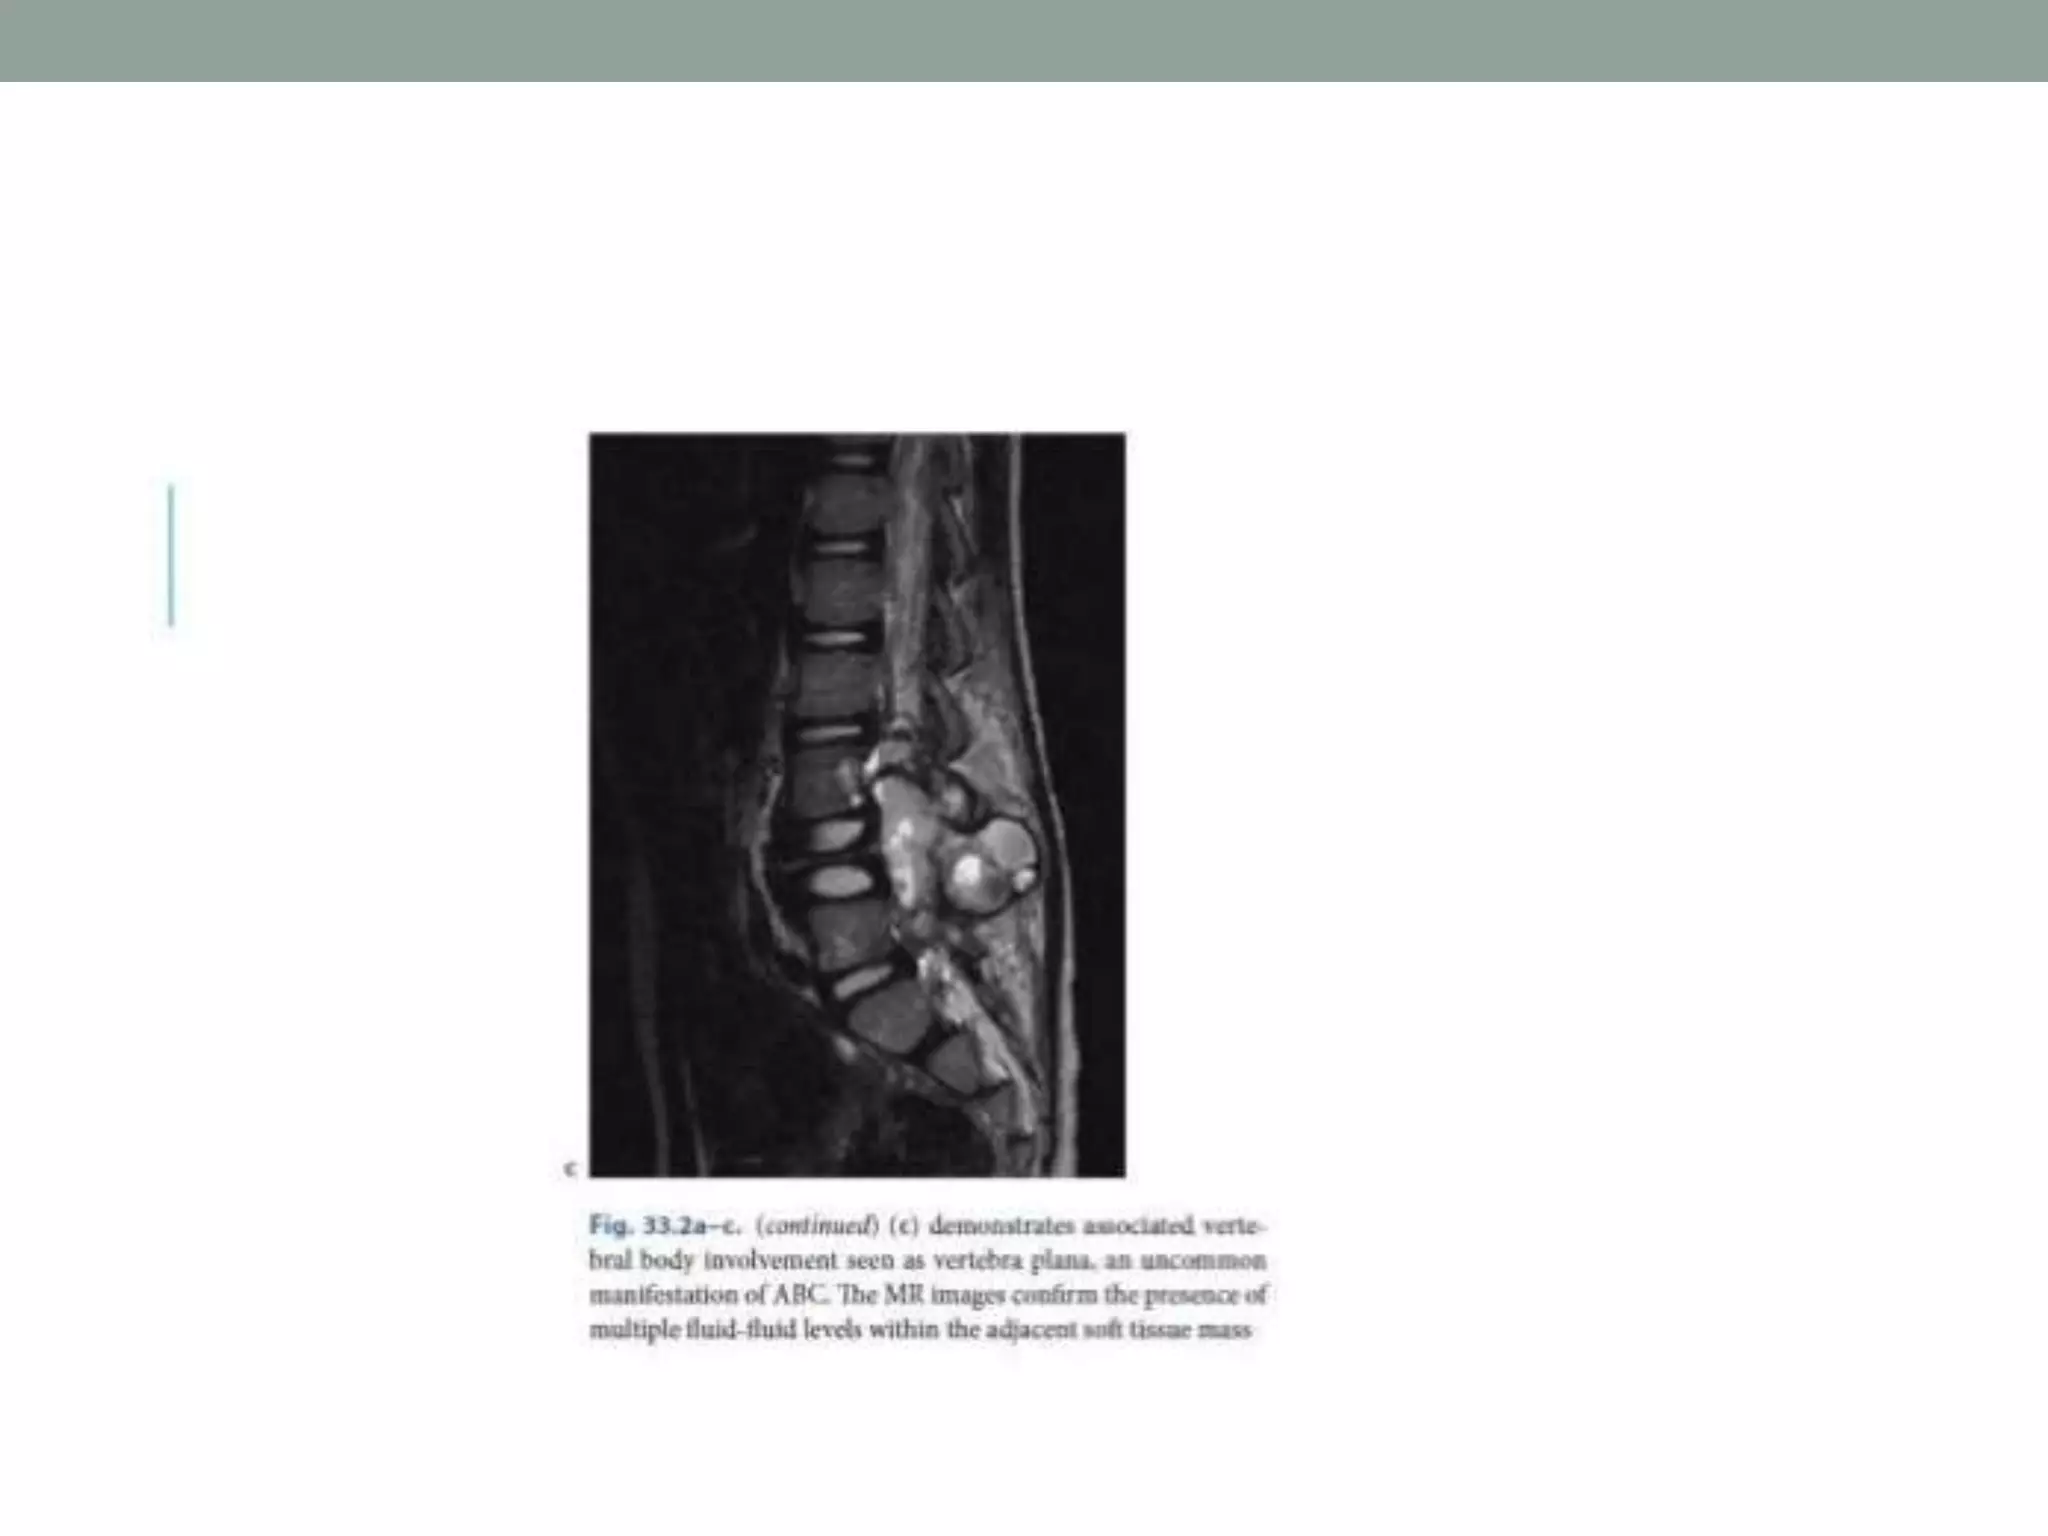

• Fluid-fluid levels were initially described at CT. MR

imaging is now the most sensitive method for detecting

fluid-fluid levels and may also help differentiate liquid from

hemorrhage.

• The imaging finding of prominent fluid-filled hemorrhagic spaces in

a vertebral lesion is suggestive of ABC but has also been described

in telangiectatic osteosarcoma. Moreover, the high prevalence of a

secondary ABC should indicate the possibility of finding fluid-fluid

levels in a coexisting tumor.